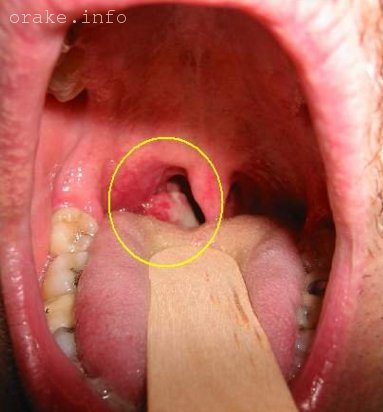

Изображение доброкачественной опухоли в носоглотке:

Новообразование в полости носоглотки у ребенка, известное как ангиофиброма, обычно является доброкачественной опухолью.

Изображение рака носоглотки: